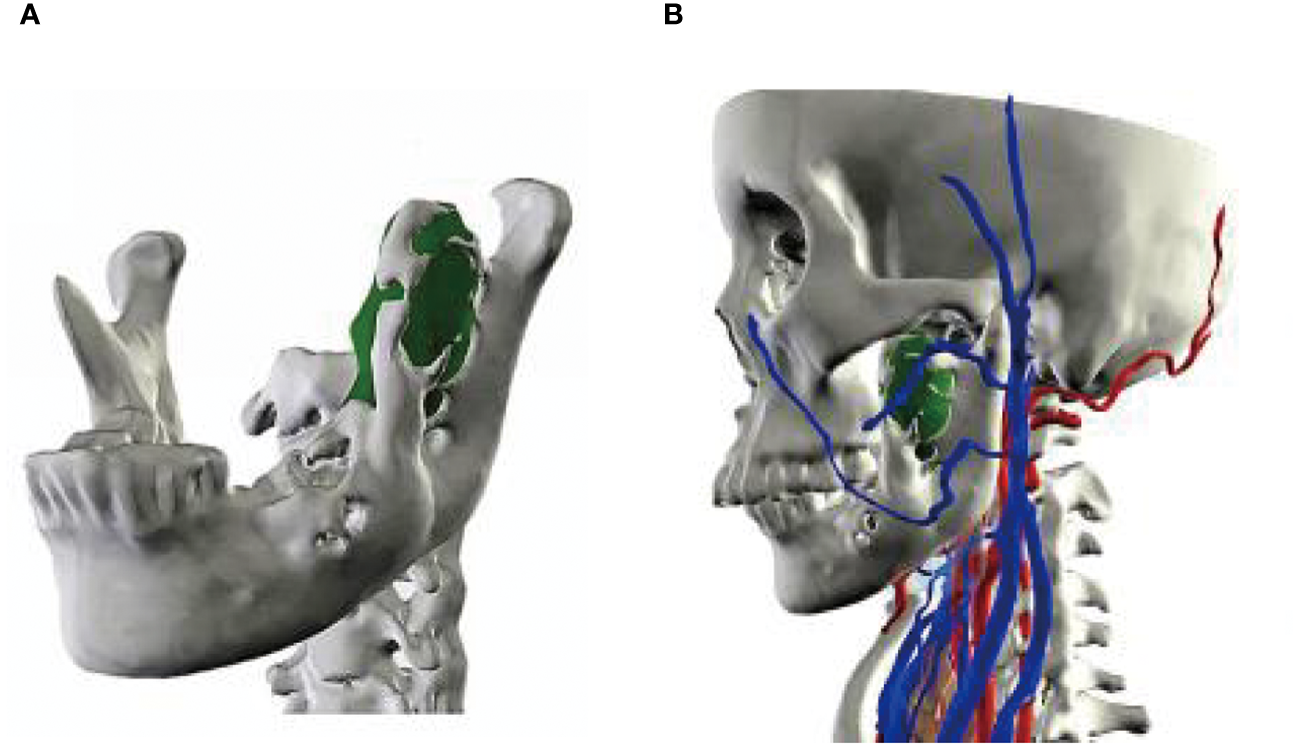

A 56-year-old female underwent surgery for ameloblastoma in the left mandible 2 years previously. Specialist examination revealed that the patient had swelling on the left face and neoplasm in the area surrounding the left mandibular angle and ramus, approximately 5.0 × 4.0 cm measuring in size. The patient also had a mild limitation in mouth opening, and 36, 37, and 38 were not detected in the oral cavity. According to the patient’s previous medical records and consultation report from the pathology department of our hospital, the pathological diagnosis of the patient was confirmed as ameloblastoma (Figure 1). The patient was diagnosed with ameloblastoma upon admission and scheduled to undergo partial mandibular resection and fibular osteocutaneous flap repair. She underwent CTA examination of the maxillofacial and the left calf prior to surgery. The obtained CTA data were imported into a software workstation for 3D reconstruction and subsequently downloaded onto a holographic display (Figures 2, 3). During the operation, the left calf was automatically positioned according to the holographic display, and the perforator vessels were dissected in real-time (Figure 4). Fibular osteocutaneous flaps were prepared to repair the mandible, and direct sutures were placed at the donor site (Figures 5, 6). After the operation, the flap fully survived, and during the 6-month follow-up, the patient expressed satisfaction with the reconstructive outcome.

Figure 2

Maxillofacial 3D model. (A, B) Lateral views of the model.